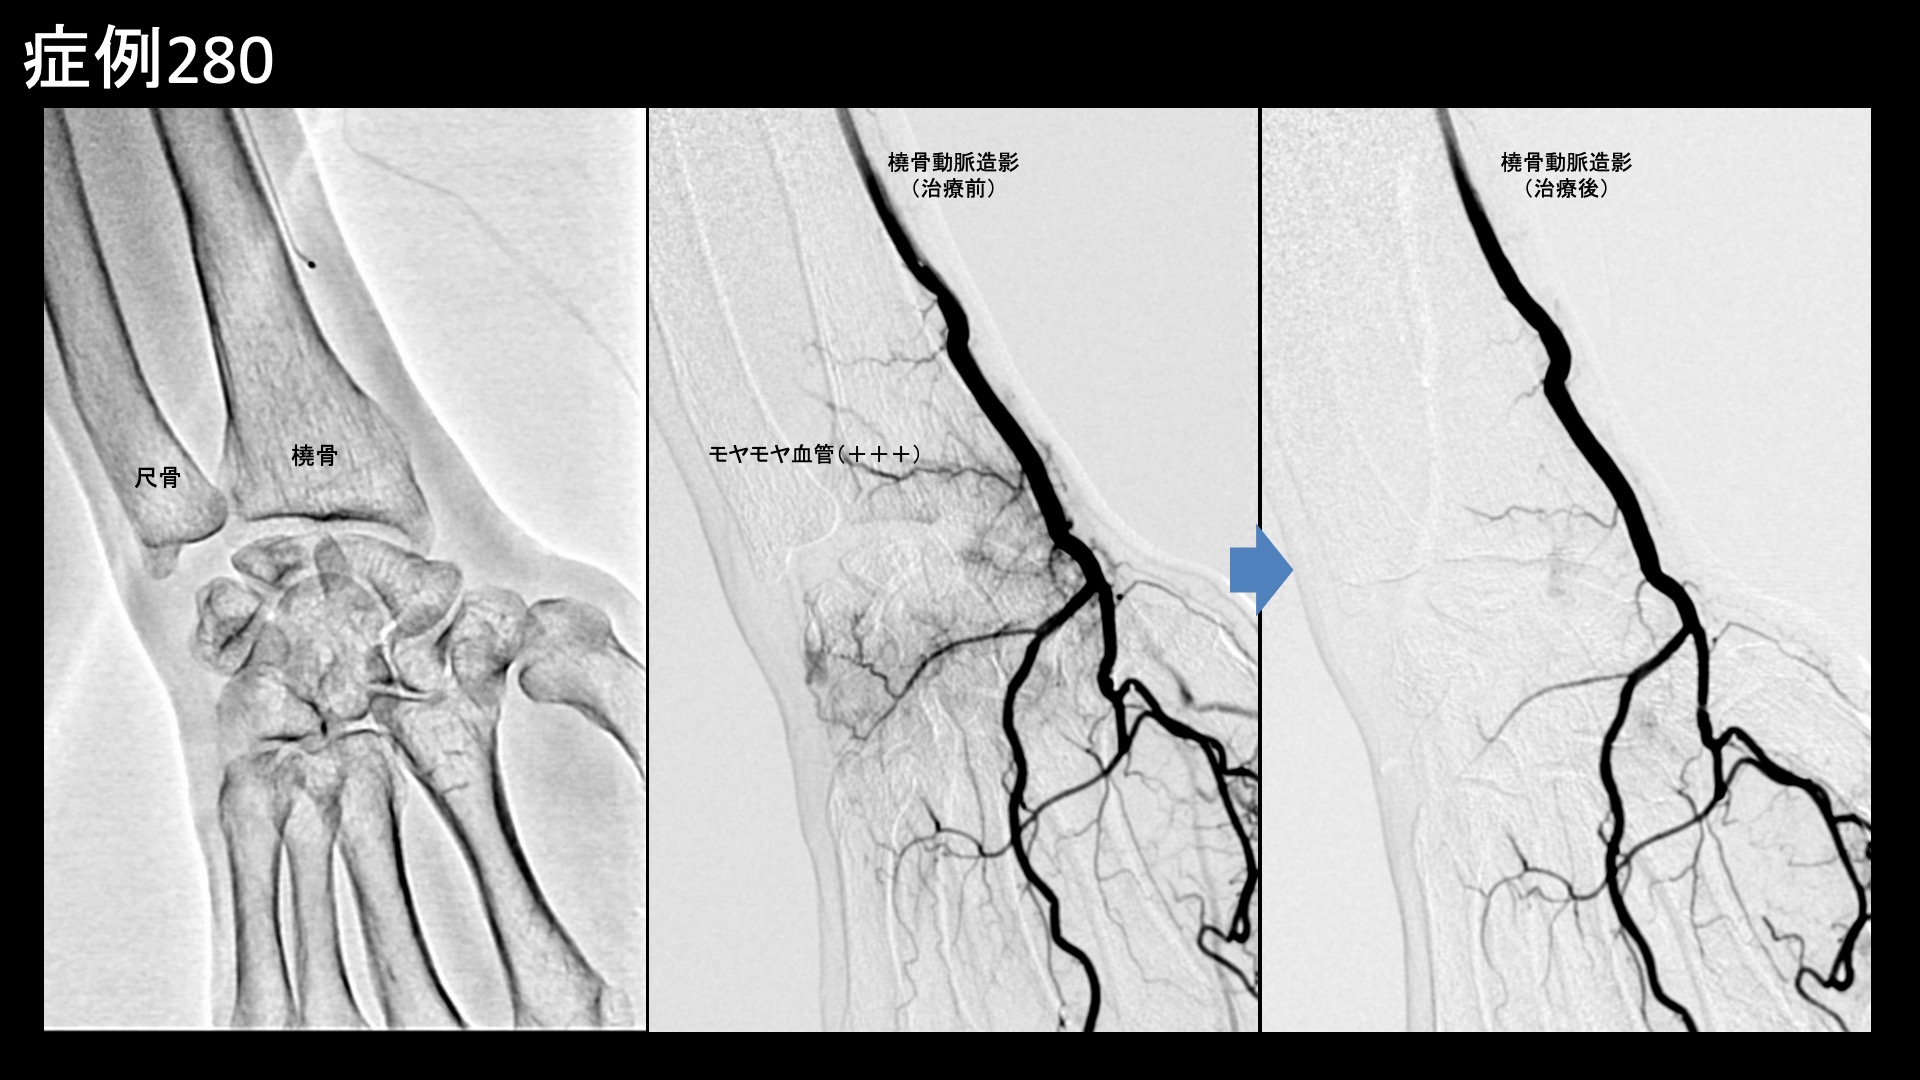

血管造影を行うと、橈骨動脈および骨間動脈にてモヤモヤ血管が濃染像として描出されました。治療後は画像上速やかに消失しました。その他複数箇所の治療を行い終了しました。

治療前画像:損傷を受ける、あるいは繰り返しのストレスにより発生した異常な新生血管

治療後画像:カテーテルを用いて塞栓物質を血管内に投与し新生血管を塞いだ状態